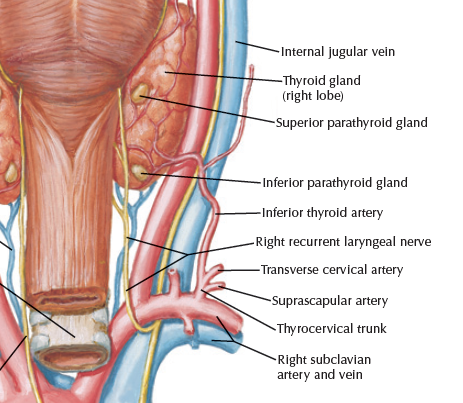

Superior thyroid artery

- Infrahyoid br.

- Sup. laryngeal a.

- SCM br.

- Cricothryoid br.

Tympanic artery

Thyrocervical trunk

SCM血液

上1/3

中1/3

- Sup. thyroid a.

- Ext. carotid a.

下1/3

- suprascapular a. (>80%)

- common carotid a. 外側,蓋在 thyrocervical trunk 上

- recurrent laryngeal n.沿 tracheoesophageal groove 攀升(就是食道和氣管中間),接觸 medial thyroid gland,向內鑽到 inf. constrictor,進入 larynx,同時支配感覺與運動

- Recurrent laryngeal n.

- 過Cricothyroid joint改叫Inf. laryngeal n.

- 支配所有軟骨間肌,除了 Cricothyroid m.

- 假聲摺以下的喉部黏膜感覺

recurrent laryngeal n.

- left: arch of aorta

- right: Subclavian a.